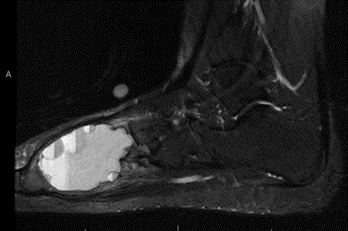

Magnetic resonance imaging (MRI) scans. MRI scans help doctors determine where the tumor begins and where it ends, which helps them to plan treatment.

While CT scans are better at visualizing the bone, MRI scans are best for looking at the tissue and fluid inside the cyst. The classic appearance of an ABC on MRI shows fluid-fluid levels which represent blood and cyst fluid layered in the bone tumor.

MRI showing classic fluid-fluid levels characteristic of an aneurysmal bone cyst.